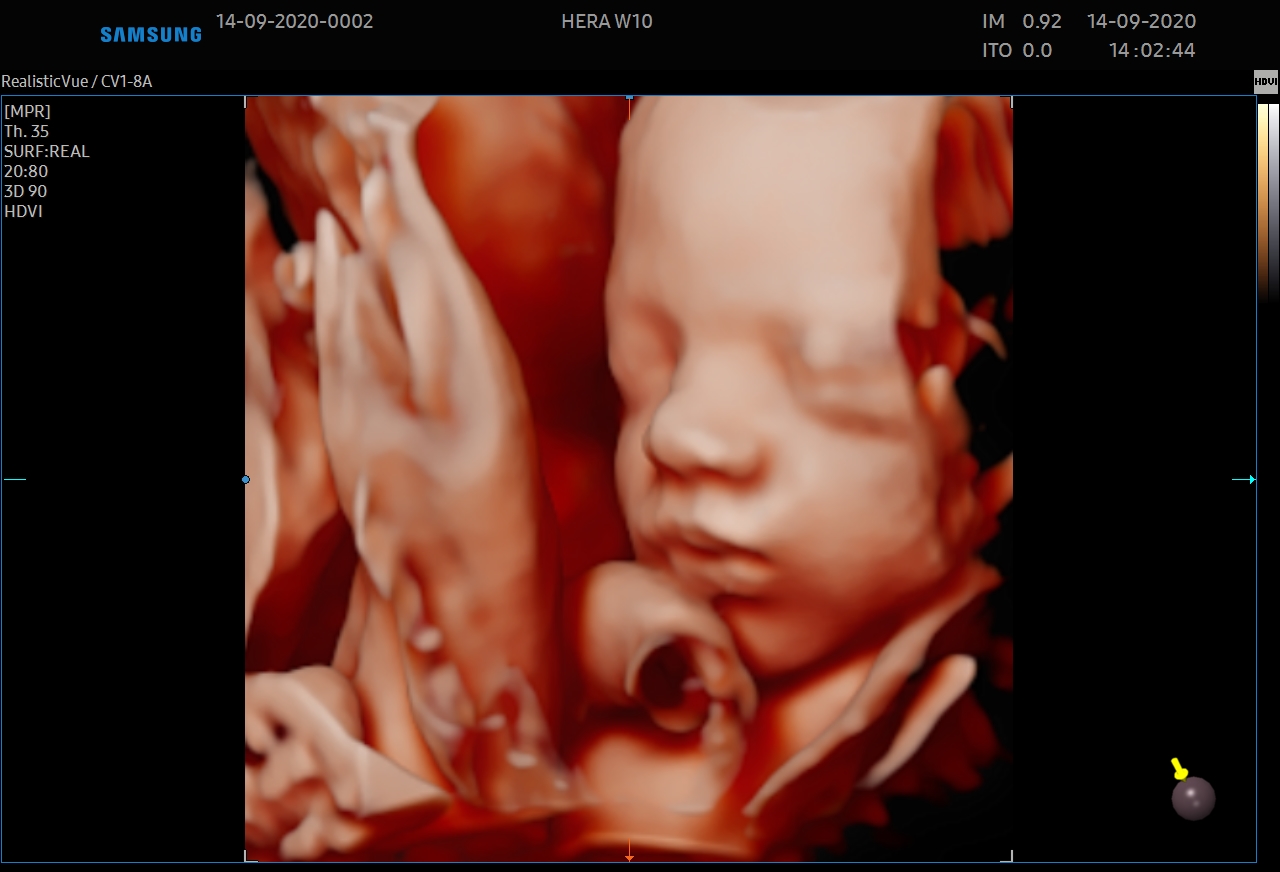

Le 5D CNS+™ est un module qui permet de générer et de reconstruire 9 plans de coupe automatiquement à partir d'une acquisition volumique sur le cerveau fœtal. Les calipers sont positionnés automatiquement par l'échographe à la demande de l'utilisateur.

5D Heart™ est un outil intelligent permettant d’établir un diagnostic cardiaque fiable grâce à la visualisation des 9 coupes essentielles, recommandées par les sociétés internationales. Couplé à l’analyse des échanges vasculaires cardiaques, il rend l’examen du cœur plus intuitif indépendamment de la position du fœtus.

Le BiometryAssist™ est une technologie de biométries semi-automatisées qui permet à l'utilisateur de gagner en efficacité et en productivité.